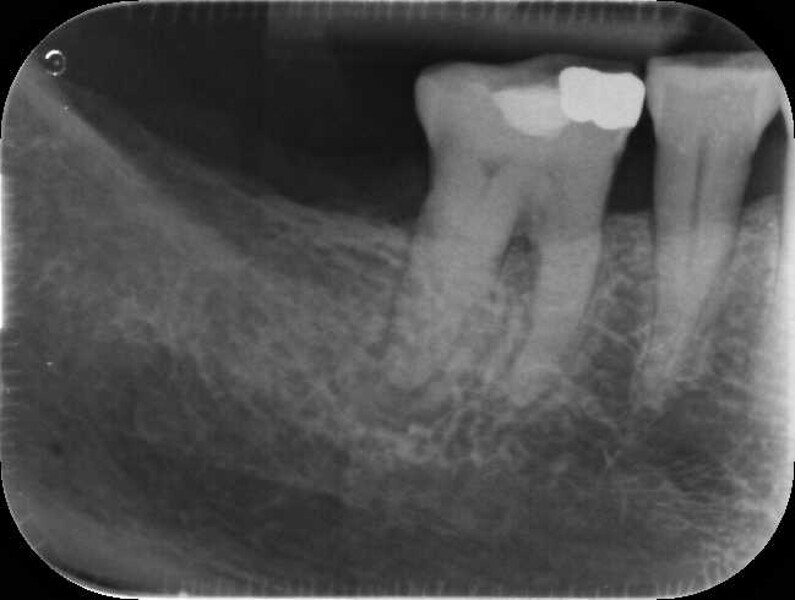

Fig. 17a: Case assisted with CBCT to determine anatomy pre-operatively. Note the multiple cross sections moving apically and the correlation to the 2-D view. Note also the conservative taper in relation to the root width. (Courtesy of Dr. Brett Gilbert)

Fig. 17b: Case assisted with CBCT to determine anatomy pre-operatively. Note the multiple cross sections moving apically and the correlation to the 2-D view. Note also the conservative taper in relation to the root width. (Courtesy of Dr. Brett Gilbert)

Fig. 17c: Case assisted with CBCT to determine anatomy pre-operatively. Note the multiple cross sections moving apically and the correlation to the 2-D view. Note also the conservative taper in relation to the root width. (Courtesy of Dr. Brett Gilbert)

Fig. 17d: Case assisted with CBCT to determine anatomy pre-operatively. Note the multiple cross sections moving apically and the correlation to the 2-D view. Note also the conservative taper in relation to the root width. (Courtesy of Dr. Brett Gilbert)

Fig. 17e: Case assisted with CBCT to determine anatomy pre-operatively. Note the multiple cross sections moving apically and the correlation to the 2-D view. Note also the conservative taper in relation to the root width. (Courtesy of Dr. Brett Gilbert)

Fig. 17f: Case assisted with CBCT to determine anatomy pre-operatively. Note the multiple cross sections moving apically and the correlation to the 2-D view. Note also the conservative taper in relation to the root width. (Courtesy of Dr. Brett Gilbert)